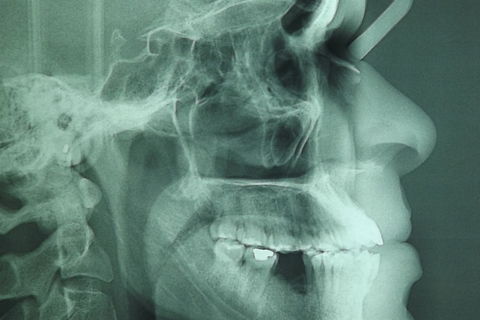

fotos iniciais do caso.

Paciente do sexo masculino, 36 anos, brauifacial. Relatava que os Diastemas lhe incomodavam muito, e em tratamento anterior o profissional fez exo de 2 incisivos centrais inferiores e instalou Prótese movel com 4 incisivos, após um tempo de uso a prótese começou a incomodar. em planejamento com o implantodontista ficou definido o fechamento dos diastemas e reabilitação dos elementos 41 e 31 com implantes.

segue as fotos do caso